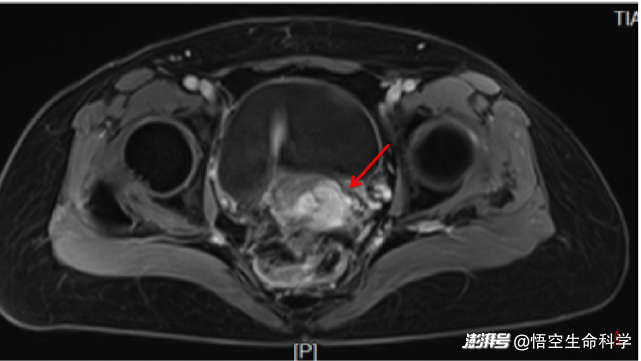

回輸前基線檢查